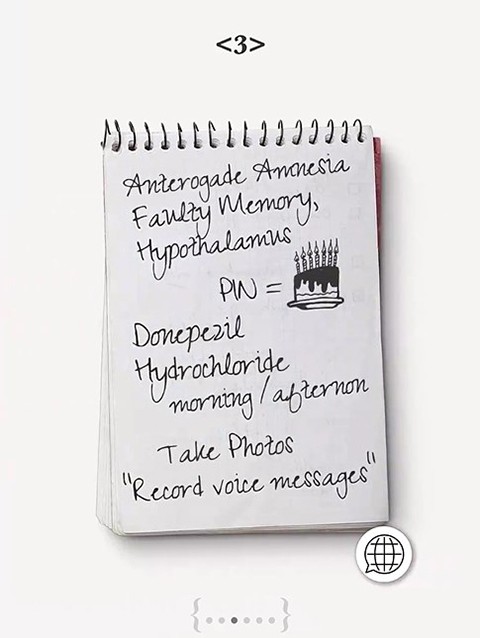

8、左滑至笔记特写,根据线索PIN,不要点翻译,可知手机PIN密码与生日有关。

9、之后左滑至腕带特写,得知生日信息8—9—61。

10、然后翻到手机处,输入密码8961解锁手机(左右箭头按钮控制按键左右位置切换,第三个按钮为确定按钮。RECALL重拨,C删除,绿色拨打,红色挂断)。